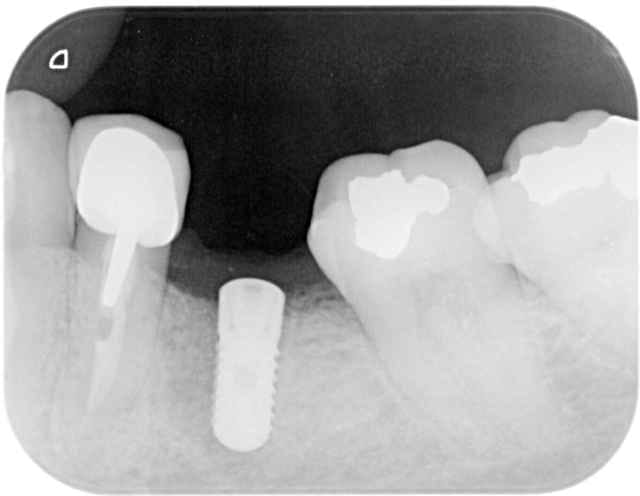

Plus sérieusement sur le premier cas le foret en place est le terminal de 12x3,5, je le trouve pas si mal l'axe 3d, mais j'ai un peu forcé sur le biomat

pour l'autre cas, je suis aussi dans l'axe,j'avais décalé le deuxieme forage en palatin pour faire une expansion

vesti, puis j'ai choisi la facilité

pxav c'est pour toi , tu te souviens

50 minutes, 3implants et 3 hemos

En 33 c'est un bouchon, j'ai tapé la corticale interne et l'artériole en meme temps et l'ai pas réussi à la traversée(l'artériole)

çà c'est un vrai probleme de 3D , vous m'avez porté la poisse

Suis moins patient que pxav, c'est un 8x3,7 je pense que çà va aller qd meme